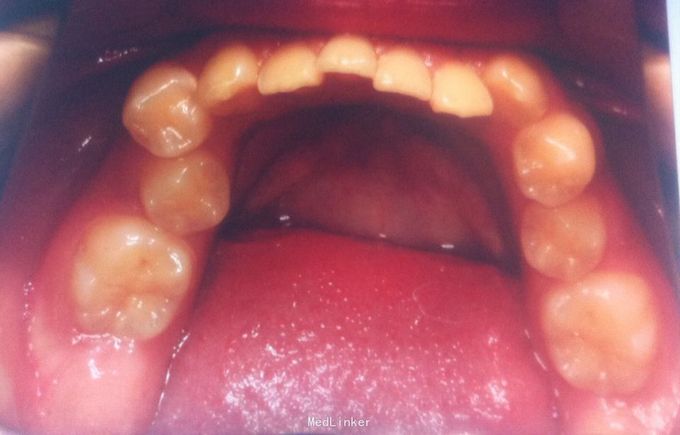

恒牙期 33,44唇侧错位 磨牙中性关系 前牙覆合2度、覆盖1度 牙列拥挤